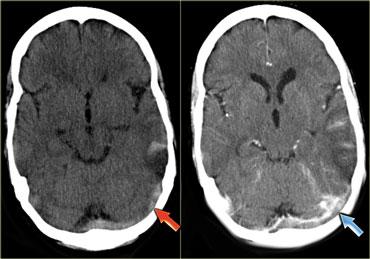

Hình ảnh giả dấu hiệu mạch máu tăng tỷ trọng

Bình thường, các tĩnh mạch có tỷ trọng cao hơn một chút so với nhu mô não, và trong một số trường hợp rất khó để xác định đây là hình ảnh bình thường hay tăng tỷ trọng thực sự.

Trong những trường hợp này, cần thực hiện CT có tiêm thuốc cản quang để giải quyết vấn đề.

Bên trái là hình ảnh xoang ngang có huyết khối và bên cạnh là xoang ngang bình thường.

Ở trẻ nhũ nhi, nhu mô não thường có tỷ trọng thấp hơn so với trẻ lớn và người trưởng thành.

Điều này dẫn đến tỷ trọng tương đối cao của máu trong xoang dọc trên so với nhu mô não, tạo ra hình ảnh giả dấu hiệu cục máu đông tăng tỷ trọng.